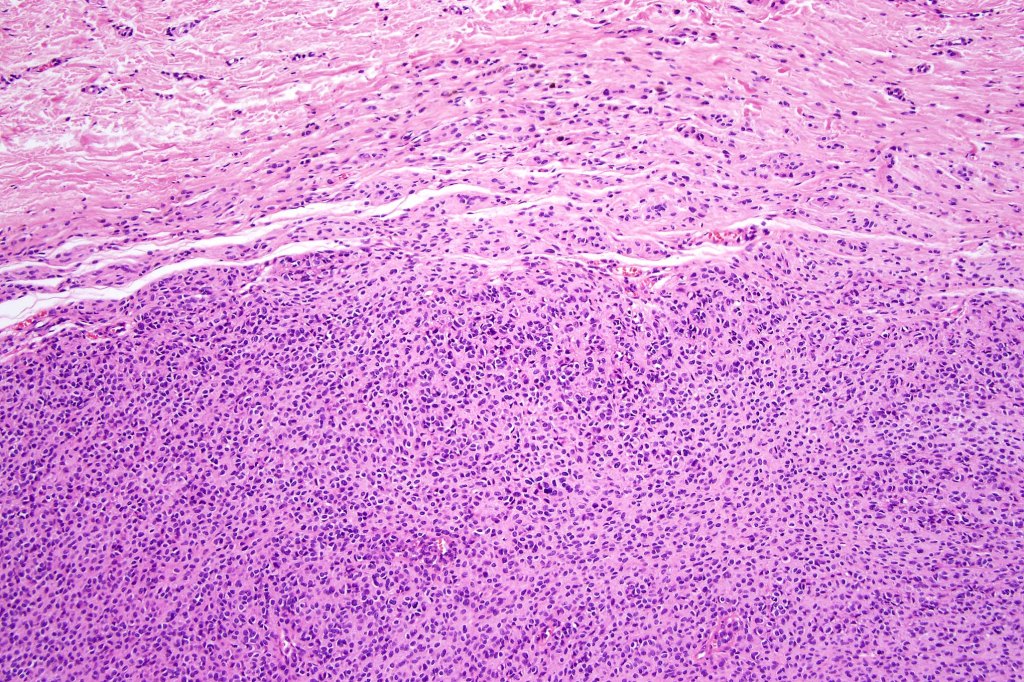

•The nodule generally merges with the adjacent nevus but sometimes it can be sharply circumscribed

•It is hypercellular and most often composed of epithelioid cells showing little pleomorphism & only occasional mitoses

•Some examples show more marked pleomorphism with prominent nucleoli and increased mitotic activity but abnormal mitoses are not a feature. These are not associated with any sinister biological potential

•Absence of necrosis, hemorrhage or Pagetoid spread in the overlying epidermis

•Spindle cell, small blue cell, blue nevus-like features, Spitzoid & proliferative nodules with mesenchymal differentiation (myofibroblastic, chondroid & osteoid) can be seen